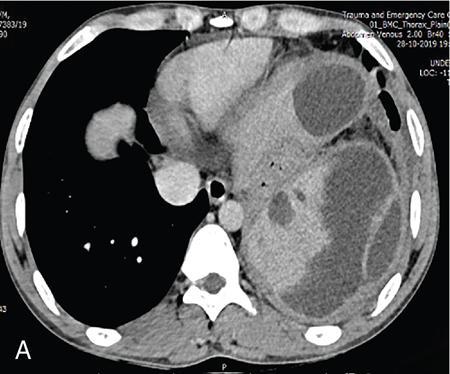

Vijay Kumar K.R. CONGENITAL SPLENIC ABNORMALITIES A multitude of variants and pathologies affect the spleen and it is pertinent for a radiologist to be aware of the common imaging appearances of the same. The spleen begins to develop in the fifth week of gestation from a mass of mesenchymal cells that condense between the two leaves of the dorsal mesogastrium. Several such aggregates fuse to form the lobulated embryonic spleen. The spleen is translocated to the upper left side of the abdominal cavity due to rotation of the stomach and differential growth of the dorsal mesogastrium. The mesogastrium fuses with the peritoneum over the left kidney and forms the splenorenal ligament. The lienorenal ligament fuses dorsally and the splenic artery courses behind the peritoneum as it enters the splenorenal ligament. The portion of dorsal mesentery between the stomach and spleen forms gastrosplenic ligament. Differentiated mesenchymal cells form the parenchyma, connective tissue and capsule of the spleen. The foetal spleen shows lobulations, which normally disappear before birth. However, they may persist along the medial part of the spleen. Sometimes a persisting portion of the spleen may extend medially and anteriorly over the upper pole of the left kidney. It may be mistaken for a space-occupying lesion arising from the kidney. Rarely it may extend posterior to the upper pole of the left kidney, displacing it anteriorly (Fig. 9.22.1.1). The notches and clefts along the superior borders are vestiges of the grooves that initially separated the foetal lobules. They may be 2–3 cm deep. They may mimic a splenic laceration in a patient with abdominal trauma, and the embedded peritoneum at the waist may simulate splenic infarction or haematoma. Hence caution should be exercised. A normal spleen which does not have a fixed ligamentous attachment can change position within the abdomen and is hence known as a wandering spleen. The spleen is normally anchored by the gastrosplenic and lienorenal ligament. Absence or weakness of one or more ligaments that affix the spleen. The spleen with its vascular pedicle as the sole attachment can become a hypermobile intraperitoneal organ. Rarely, the spleen may be normal in position with a wandering accessory spleen. Pregnancy (due to hormonal effects), prune belly syndrome, splenic cysts, malaria, Hodgkin’s disease and lymphangioma. Some of the affected patients may be asymptomatic and diagnosis may be incidental. Clinically it presents as a mobile, palpable, notched mass. Pressure on the vascular pedicle or torsion causes symptoms such as acute abdominal pain, nausea and vomiting. Torsion involving the tail of the pancreas may present as pancreatitis. Confirms the absence of spleen in the left upper quadrant of abdomen with identification of splenic tissue at an ectopic site. Power Doppler, colour Doppler and duplex sonography allow for the identification of blood flow in the splenic vessels and parenchyma. Intermittent torsion may be responsible for an enlarged spleen. Pathognomonic feature of wandering spleen is absence of the spleen in the upper abdominal cavity and presence of a well-demarcated, homogeneously enhancing mass of soft tissue in the pelvis or abdomen. Sometimes a wandering accessory spleen can be visualized as a long vascular pedicle connecting a small mass to the splenic vessels (‘jokari sign’). It can locate ectopic splenic tissue and can also indicate the viability of the tissue. Splenic vessel anatomy can be well demonstrated. 99mTc-sulphur colloid scintigraphy and heat denatured 99mTc-labelled red blood cell imaging provide useful information regarding size and location of splenic tissue. Torsion is indicated by lack of tracer activity in a previously demonstrated wandering spleen. Twisting and torsion of splenic artery can be demonstrated by celiac arteriography. The venous phase may demonstrate splenic vein obstruction with collateral circulation and varices. A congenital focus of normal splenic tissue that is separate from the main body of the spleen is known as an accessory spleen. It results from the failure of fusion of some embryonic splenic buds within the dorsal mesogastrium. Its incidence varies from 10% to 30% on autopsy examinations. They vary from a few millimetres to several centimetres in diameter. They most commonly are found around the splenic hilum. The second most common location is the pancreatic tail. They can also be found in the stomach wall, omentum, mesentery, large bowel and scrotum. Reveals a round or oval mass of tissue around the splenic hilum that is isoechoic with the main spleen. On noncontrast images they are isodense to the main spleen. CECT reveals serpiginous enhancement on arterial phase followed by homogeneous enhancement on venous phase-like spleen (Fig. 9.22.1.2). Accessory spleen is mildly hypointense to the spleen on T1 images and isointense on T2 images. Contrast administration reveals enhancement similar to that of spleen on the arterial, portal and late phases. It is isointense to spleen on DWI images with similar ADC values. 99mTc-sulphur colloid scintigraphy and heat denatured 99mTc-labelled red blood cell imaging show functional uptake in splenic tissue and differentiate splenule from other masses. PET CT-FDG avid mass can mimic tumour. Surgical resection is the preferred mode of treatment in the background of hypersplenism or lymphoma. It is characterized by an ectopic splenic tissue or an abnormal connection between the gonad and the spleen. The left side is more commonly involved than the right side. The accepted theory is that splenic gonadal fusion occurs due to abnormal attachment of the splenic anlage in the left dorsal mesogastrium with the left urogenital fold, during the fifth to eighth weeks of gestation. It has a higher male preponderance and can interfere with left testicular descent and closure of processus vaginalis. It commonly presents as inguinal hernia and cryptorchidism. The spleen and gonad are attached by a fibrous or splenic cord across the peritoneal cavity. It is associated with limb defect syndrome, cleft palate, micrognathia, anal anomalies, craniosynostosis, spina bifida, cardiac malformations, thoracic malformations and diaphragmatic hernias. This is not associated with congenital anomalies. Shows a well-defined scrotal mass with echotexture similar to that of spleen. Confirms splenic tissue in inguinal or scrotal area. It is characterized by the absence of spleen with duplication of right-sided structures. (Right isomerism). It has a slight male preponderance with an incidence of 1 in 40,000 live births. It has a poor prognosis due to its high association with congenital cardiac abnormalities (Fig. 9.22.1.3). It is of uncertain aetiology, and maybe associated with the mutations of CFC1 gene, SHROOM3 gene etc. Delayed development of embryonic curvature can be another cause. It is also theorized that it can be caused due to vascular compromise by pressure on splenic blood supply from adjacent structures. Splenectomy – Usually has a surgical history and is not accompanied by associated anomalies. It is a heterotaxy syndrome associated with multiple spleens and duplication of left-sided structures. (Left isomerism). It has an equal gender predilection with a slightly higher female preponderance. It has a fairly better prognosis than asplenia and is associated with a lesser incidence of cardiovascular anomalies (Fig. 9.22.1.4). It is of uncertain aetiology, and maybe associated with the mutations of CFC1 gene, SHROOM3 gene etc. Accelerated development of embryonic curvature can be another cause. SPLENIC INFECTION AND ABSCESS The infection of the spleen can show three patterns. Fungal and granulomatous infections usually present with multiple micronodules. A pyogenic abscess usually manifest as a solitary lesion. Imaging of diseases causing splenic nodules is never the sole basis for diagnosis. The clinical presentation and laboratory testing (tumour markers, tuberculosis testing and bone marrow biopsy) help in establishing an accurate diagnosis. The imaging findings are nonspecific and the nodules may vary in size from a few millimetres up to 2 cm in diameter. They maybe hypoechoic on ultrasound and hypoattenuating on CT. They are of low signal intensity on T1-weighted sequences and vary from hypointense to hyperintense on the T2-weighted sequences. The nodules show no enhancement or show ring enhancement after contrast study. Healed granulomas are seen as scattered, discrete, small calcifications in an otherwise normal spleen. With increasing number of immunocompromised patients, such as oncology patients undergoing aggressive chemotherapy, critically ill patients in intensive care units, injection drug abusers, and HIV-infected patients, there is rise in the incidence of splenic abscess. For splenic abscess to develop, it may require the presence of bacteremia (sepsis and septic emboli) and altered splenic architecture, which is caused secondary to a haematoma, infarct, or sickle cell disease. Abscesses can also develop from the extension of infection from adjacent organs, like in cases of infected pancreatitis and perinephric abscess, which are less common. In about 20% of cases, cause or source could not be discovered. Abscesses can be unilocular or multilocular, solitary or multiple, depending on the causative organisms and patient’s immunity. Mortality ranges from 15% in otherwise healthy patients with unilocular splenic abscess to 80% in immunocompromised patients with multiple abscesses. Abscesses which are multilocular, gas-containing or due to gram-negative bacillus show poor prognosis. A pyogenic abscess is usually solitary, unilocular/multilocular, but it can also be multifocal. These are uncommon and are reported in 0.14%–0.70% of large autopsy series. Most common presentation is fever (92%), left upper abdominal pain (77%) and leucocytosis (66%). Other symptoms are left pleural effusion and splenomegaly. It can be solitary or multiple, unilocular or multilocular. The appearance of splenic abscess depends on the stage of development. In the early stages of the disease, an abscess appears as an ill-defined mass later developing into a complex collection with septations, debris and sometimes gas. In later stages, after a capsule is developed, the lesion becomes well defined. Left pleural effusion is seen in around 42% of cases. Left lung base atelectasis in 20% of cases and splenomegaly is seen. Abscess with air can be identified based on the presence of extraluminal gas or air–fluid levels in the left upper quadrant. Ultrasonography has a sensitivity of 75%–98% in detecting splenic abscess. This is a very useful modality in patients who are bedridden, with renal impairment and for assessment of small splenic lesions (Fig. 9.22.2.1). Ill-defined hypoechoic mass mimicking a mass is seen in the early phase of the infection and a complex mass with internal septations, debris, rarely acoustic shadowing caused by gas is seen in later stages. The capsule appears as a thin hyperechoic rim. It is noninvasive, speedy, and a modality with high sensitivity (92%–98%). It helps in differentiating unilocular from multilocular lesions and, gives exact anatomical localization and information about perisplenic area, which later helps in planning-guided management procedures. An abscess is seen as a hypodense collection or complex cystic lesion with enhancing rim on the postcontrast study (Fig. 9.22.2.2). CT may help in identifying concurrent areas of infection and, thus, the source of infection. On CT, an abscess may look similar to an infarct, haematoma, or neoplasm. An infarct lacks mass effect, unlike abscess or tumour (Fig. 9.22.2.3). The presence of gas within the lesion is diagnostic of abscess; however, this finding is rare. Splenic abscesses show low signal on T1-weighted images and high signal on T2-weighted images compared with the normal spleen. Minimal to intense peripheral enhancement is seen after IV administration of gadolinium. But MRI is not routinely done, as many patients are clinically unstable. This plays a limited role in the detection and localization of splenic abscess. A nonspecific filling defect is seen on a 99mTc-sulphur colloid scan within spleen if the size is more than 2 cm in diameter. Normal inherent splenic activity on 67Ga scans and 111In-labelled leukocytes scans obscures any kind of inflammatory focus in the spleen, giving rise to false-negative examination. 67Ga scans are nonspecific as tracer uptake can be seen in neoplastic conditions such as lymphoma. Detection and characterization of the abscess are better done if 99mTc-sulphur colloid scan is done prior to 111In-labelled leukocytes scan. FDG PET/CT can also detect the site of infection but not used in the diagnosis of splenic abscess. Early diagnosis of an abscess is prompted for a better outcome. Based on laboratory findings, appropriate antibiotic therapy initiated. USG or CT-guided percutaneous aspiration is tried if the abscess is less than 5 cm in size, and for larger abscesses, percutaneous drainage procedures are done preserving the spleen. Splenectomy is reserved for complicated infections. Fungal abscesses are usually seen in immunocompromised patients with neutropenia such as patients with acquired immunodeficiency syndrome (AIDS), on chemotherapy and immune suppressive agents, and with lymphoproliferative disorders. With the advent of aggressive chemotherapy, the incidence of splenic fungal infections has increased. Approximately 7% of patients with acute leukaemia have hepatosplenic fungal infections. Multiple microabscesses are common. Hepatosplenic candidiasis lesions are very small, and before the advent of CT and MRI, their detection was too difficult. They measure in the range of 5–10 mm in diameter; however, they may be even miliary (<5 mm). Infections are mostly caused by candida species. Other organisms are aspergillus, Histoplasma and Cryptococcus. Imaging characteristics depend on the stage and severity of neutropenia. In cases of chronic disseminated infections with poor neutrophil counts, sometimes lesions are not visible as the host fails to produce an immune response. Lesions become apparent once neutrophil counts improve. Patients presenting with fever and splenomegaly are not improving on conventional antibiotic therapy, and with associated immunocompromised status, fungal infections are to be considered. No single imaging is specific or sensitive in establishing the diagnosis. Serial imaging is needed to detect hepatosplenic involvement; however, tissue diagnosis is the gold standard. Four different patterns are seen in hepatic candidiasis. Multiple, small, homogeneous hypoechoic nodules are the most common finding. Less commonly wheel-within-a-wheel appearance (i.e. the target sign) is seen in the early stage of infection. The first wheel is the peripheral hypoechoic zone of fibrosis and an echogenic second wheel of inflammatory cells around a central hypoechoic nidus containing necrosis and fungal elements. Later these lesions evolve into Bull’s eye lesion where there is a central echogenic focus surrounded by a hypoechoic halo. Lesions become small and hyperechoic with various degrees of posterior acoustic shadowing, with or without calcification, or they may even disappear later in the course of the infection. Splenic nodules are hypodense lesions measuring in the range of 5–10 mm. Only 30% of cases are detected in noncontrast studies. They often have low attenuation, although there can be a focus of high attenuation or a ‘wheel-within-a-wheel’ pattern. Peripheral ring of enhancement is noted in around 70% of cases in the arterial phase of CT, and it is said to disappear on the portal venous phase. There is no significant difference in the detection of the lesions between arterial and portal venous phases of contrast studies. MRI is said to be the investigation of choice for diagnosis of hepatosplenic candidiasis and is superior to CT and USG, especially when short-time inversion recovery sequence is used. MR imaging is also used to monitor the response to antifungal therapy. Based on MRI findings different phases of hepatosplenic candidiasis are described. Lesions are small, measuring less than 1 cm in diameter. They show mildly hypointense on the T1-weighted images and markedly hyperintense on the T2-weighted images. In 2 weeks to 3 months, acute lesions are transformed into subacute lesions. The lesions reveal mildly increased signal on both T1- and T2-weighted sequences. On all sequences, a peripheral ring of very low signal intensity is seen. Following the gadolinium administration, the central region of the lesions show enhancement; however, the peripheral ring continues to have low signal intensity, making them more obvious. It takes from 3 months to more than 1 year for the healed fungal foci composed of fibrous tissue of differing densities and degrees of vascularization to appear on MRI. The lesions measure 1–3 cm, become irregular, and the central area disappears. Chronic healed fungal abscesses have low signal intensity on T1-weighted images and are isointense to mildly hyperintense on T2-weighted images. No perilesional dark ring is noted. These lesions are moderately hypointense on early postgadolinium images and minimally hypointense on delayed postgadolinium images. Mycobacterial tuberculosis infections are mainly seen in immunocompromised patients. Spleen involvement is seen in disseminated, miliary infection in about 80%–100% of autopsy cases; however, it is documented less on imaging. Splenic tuberculosis is seen in the form of nodules measuring ∼ 0.2 and 1 cm in diameter. The macronodular form is very rare (Fig. 9.22.2.4). Hypoechoic pattern is seen. Hypoattenuating nodules with lymphadenopathy noted. Depending on the different stages of the tubercular process, intensities on T1- and T2-weighted images vary. On contrast-enhanced T1-weighted images, lesions most often show peripheral enhancement less commonly gradual peripheral enhancement with complete filling is noted. It is also called as Mycobacterium intracellulare infections. These are also typically seen in immunocompromised patients. Splenomegaly with multiple, low attenuation nodules is seen. Associated findings such as hepatosplenomegaly, diffuse jejunal wall thickening and enlarged lymph nodes are seen. Lymph nodal involvement is homogeneous as opposed to Mycobacterium tuberculosis infections. Focal splenic or hepatic lesions are noted in about 30% of patients with HIV who are infected with M. tuberculosis but are rarely noted in those infected with M. avium intracellulare. Marked splenomegaly is more common in M. avium intracellulare than in M. tuberculosis infection. It is a common opportunistic infection in patients with HIV. Extra pulmonary involvement manifested in the form of necrotizing granulomas. Spleen involvement is an incidental finding. When treated the nodules may enlarge and become progressively calcified in a rim like or punctate fashion. Disseminated infection can show punctate calcification in adrenal glands, pleural or peritoneal effusions, that subsequently calcify. Splenomegaly with small hypoechoic lesions with cystic components or tiny, highly reflective, nonshadowing foci or calcified granulomas. The nodules are hypodense. Calcified granulomas are seen in later stages. This is a self-limited disease caused by bartonellae henselae. Hepatosplenic involvement is rare. This disease is to be considered when a patient presents with abdominal pain, fever of unknown origin, and multiple hypodense lesions in the liver and spleen. It is also called as echinococcosis, a disease seen in endemic regions and in patients emigrated from endemic areas. The causative organism is a zoonotic tapeworm echinococcus granulosus. The most commonly involved organs are the liver, lung, peritoneum, kidney, brain, mediastinum and heart. Spleen is rarely primarily involved. Spleen is involved in approximately 2% of cases of abdominal hydatidosis. Spleen involvement is seen in case of an extensive abdominal hydatidosis, like after the rupture of liver hydatid cyst or in cases of systemic dissemination of infection. Larvae of the tapeworm incite an inflammatory response after its entry into the target tissue in the host where it forms a hydatid cysts consisting of three layers. Peri cyst is an outer layer of modified host cells forming a dense and fibrous layer. The middle layer laminated layer and an inner germinal layer made up of daughter cysts, also called as brood capsules. Scolices develop in the brood capsules. The laminated and germinal layer forms the true cyst wall. After the parasites die, the cysts become inactive, may calcify, and undergo fibrosis. Patients present with abdominal pain, splenomegaly and fever. The diagnosis is to be suspected in all patients from endemic areas presenting with a splenic cyst. A World Health Organization Working Group on echinococcosis has a standardized sonographic classification of echinococcal cysts (Table 9.22.2.1). CE, cysticechinococcosis; CL, undifferentiated simple cystic lesions. Radiological appearances depend on the natural aging process of the cyst. Classic imaging characteristics are lost when the cyst becomes secondarily infected. A ring-like or curvilinear calcification noted in the left hypochondriac region. This may represent the calcification of pericyst in later stages of the disease. Ultrasound is an easy and most commonly used for evaluation of a suspected case of abdominal echinococcal disease. It is used for the diagnosis, planning the management and follow-up. Shifting of brood capsules within the cyst causes fine internal echoes, that is ‘The snowflake sign’ (hydatid sand). Detached laminated endocysts may be seen within the cysts, that is ‘The. Waterlily sign’. Mother cysts may be partially /completely filled by daughter cysts. Calcifications with posterior acoustic shadowing are seen in later stages of the disease. CT and MRI are indicated for widespread disease and complications and for planning percutaneous therapy and surgery. Complications of a hydatid cyst include compression of the adjacent structures, cyst rupture, secondary infections, anaphylaxis and fistulization to surrounding structures. A hydatid cyst may be seen as a well-defined, hypoattenuating cystic lesion with fluid-attenuation values and a distinguishable wall. CT is more sensitive for subtle wall calcification. May appear hyperdense because of debris, hydatid sand and inflammatory cells (Fig. 9.22.2.5). In CE 2 cysts, peripherally arranged daughter cysts, completely fill them other cyst. The daughter cysts show lower attenuation than the mother cyst. Type CE 3 lesions are round or oval with occasional calcification and daughter cysts. They usually show high attenuation. Type CE 4 cysts are complex masses. Intravenous contrast administration reveals enhancement of septa and cyst wall. Type CE 5 cysts are complex cystic or solid-looking lesions, and they can be partially or completely calcified. The simple cysts show low signal on the T1-weighted images and markedly hyperintense on the T2-weighted images. The rim sign which is a low signal intensity rim well seen in T2-weighted MRI images is characteristic of hydatid disease. Enhancement of septa and cyst wall is noted after the intravenous administration of gadolinium. On T1- and T2-weighted images, the maternal matrix appears hyperintense relative to the daughter cysts. The collapsed parasitic membranes may show serpent sign or snake sign, which are hypointense on all sequences. Hypointensity on T1- and T2-weighted images are seen in type CE 4 and CE 5 cysts. The imaging findings combined with the clinical, immunologic testing and epidemiologic results, usually provide the correct diagnosis. Seen in cases of tuberculosis, histoplasmosis, less commonly in Pneumocystis jirovecii pneumonia and brucellosis. These are incidental findings usually preceded by hypoattenuating microabscesses. Microabscesses heal with or without preceding regression. More than five calcifications usually represent histoplasmosis, whereas less than five represent tuberculosis. A ring-like calcification is seen in Pneumocystis carinii pneumonia. Any granulomatous infection is more likely to involve other organs such as the liver, kidneys and lymph nodes. Hydatid cysts can show ring-like or curvilinear calcification (Fig. 9.22.2.6). SPLENOMEGALY AND HYPERSPLENISM Splenomegaly is often a nonspecific finding, and there are many causes for splenomegaly. The spleen can grow into large sizes towards right iliac fossa, crossing midline. On average adult spleen measures <11 cm in length,<7 cm wide,<5 cm thick, and weighs approximately 150 g (80–300 g). The size and weight of the spleen decrease with advancing age. Spleen size is significantly influenced by the sex and body height of an individual. Chow et al. assessed 1230 healthy volunteers and found that spleen length and volume were significantly and independently associated with sex, body height and weight. Taller and heavier male individuals have larger and longer spleens. In one study the spleen length in 6% of women, and 26% of men exceeded a strict upper limit of normal of 12 cm. Rosenberg et al. established an upper limit of standard splenic length of 12 cm for girls and 13 cm for boys (≥15 years). Massive splenomegaly is defined as a spleen size greater than 18 cm, is less common and includes haematological disorders and infections (Table 9.22.3.1).